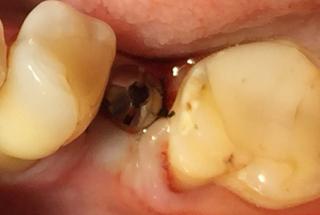

Clinical cases

MPI closely monitors clinical cases in the market to ensure their correct functioning and successful outcome.